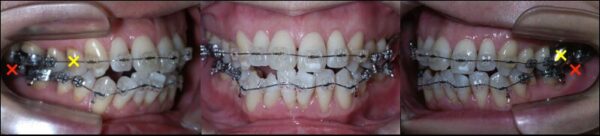

矯正治療開始時の状態です。

矯正治療開始後7か月の状態です。